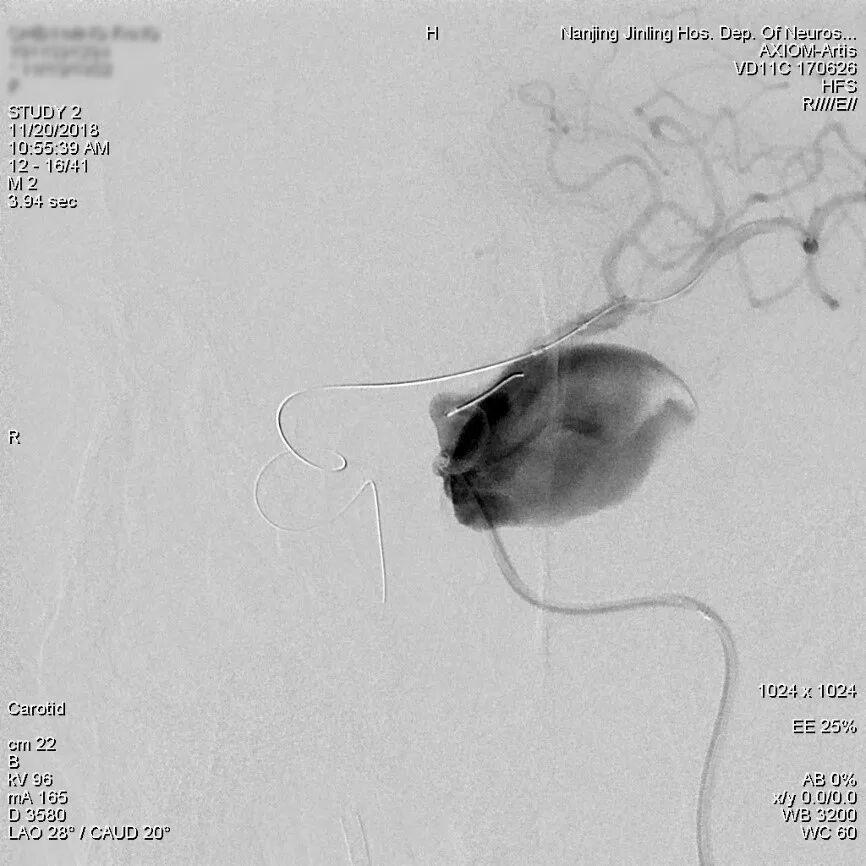

充盈球囊后锚定Marksman微导管,顺利将Pipeline Flex输送通过瘤颈至左侧大脑中动脉M1段。

为什么要用到微导管张鑫教授:“球囊锚定微导管辅助到位”技术在Pipeline Flex治疗复杂动脉瘤手术中的应用_https://www.jmylbn.com_新闻资讯_第6张

充盈球囊

等到微导管位置稳定后,泄球囊,开始释放Pipeline Flex。

最后造影显示载瘤动脉通畅,瘤内血流有滞留。3D重建示支架贴壁良好。

为什么要用到微导管张鑫教授:“球囊锚定微导管辅助到位”技术在Pipeline Flex治疗复杂动脉瘤手术中的应用_https://www.jmylbn.com_新闻资讯_第12张

支架释放后造影,瘤内血流明显减缓,造影剂滞留

3D重建示支架全程贴壁良好